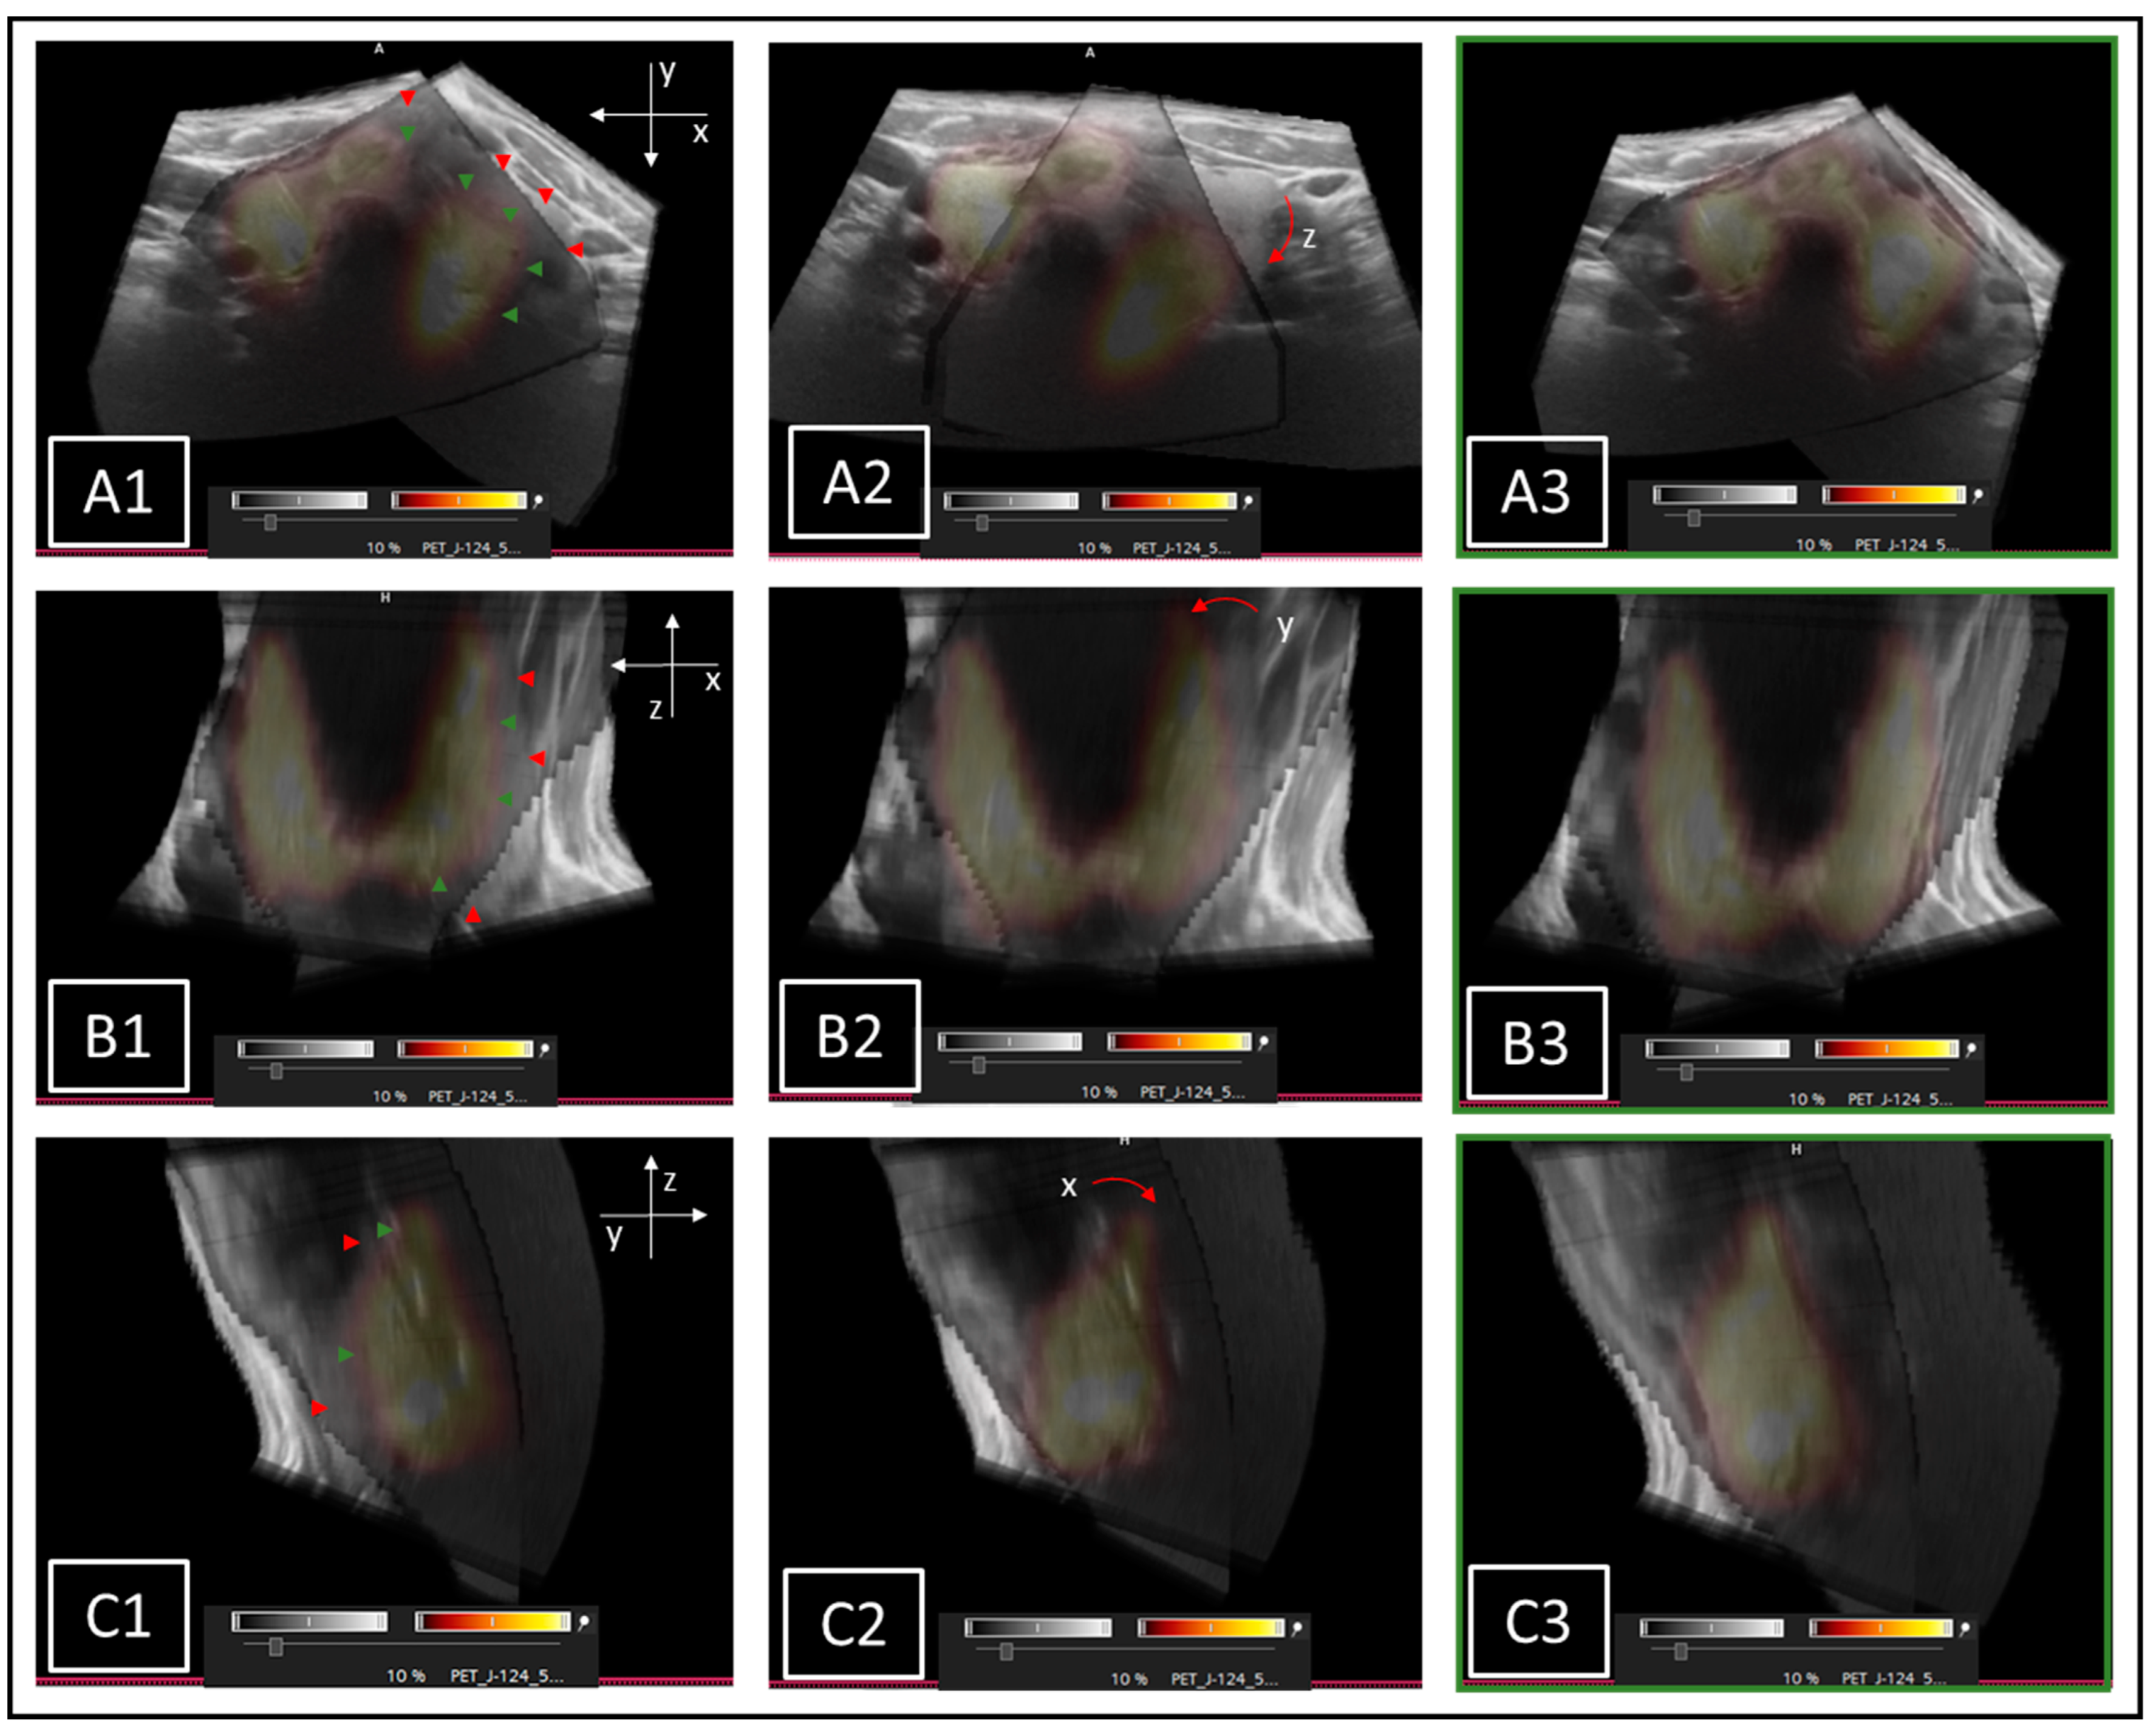

The finished stitched 3D-US data sets could then be transferred to the clinical software Syngo.via (version VB50B, Siemens, Erlangen, Germany). Herein, secondary fusion with the available I-124-PET scans was conducted, allowing a precise assessment of the anatomical correctness of the 3D-US stitching process. According to the findings, respective corrections were performed on PMOD software and again re-evaluated by I-124-PET fusion imaging on Syngo-via software (Figure 3).

Figure 3.

Stitched 3DsnUS data sets superimposed to I-124-PET images. Examples of necessary alignment corrections (red and green arrows) on transversal ((A1): shifts on x- and y-axes; (A2): rotation on z-axis), coronal ((B1): shifts on x- and z-axes; (B2): rotation on y-axis), and sagittal plane ((C1): shift on z- and y-axes; (C2): rotation on x-axis). Corrected final results are shown in (A3,B3,C3).